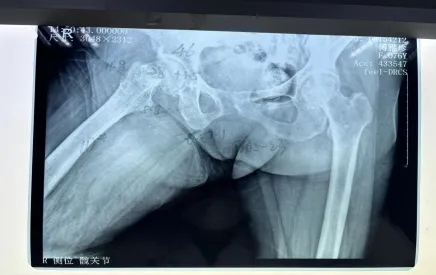

但不幸再次降臨,阿婆在家起床時(shí)不慎摔倒,右髖部疼痛難忍,經(jīng)過(guò)醫(yī)院檢查后確認(rèn),傅阿婆為右側(cè)股骨頸骨折。

阿婆住院后,羅院長(zhǎng)立馬聯(lián)系內(nèi)科和麻醉科專(zhuān)家來(lái)會(huì)診,積極調(diào)整阿婆各項(xiàng)不理想指標(biāo),盡量將手術(shù)風(fēng)險(xiǎn)降到最低。羅院長(zhǎng)還針對(duì)阿婆病情特殊情況進(jìn)行一對(duì)一的計(jì)算機(jī)三維精準(zhǔn)規(guī)劃,精心打造出詳細(xì)的手術(shù)方案,經(jīng)過(guò)羅院長(zhǎng)手術(shù)團(tuán)隊(duì)的努力,阿婆成功完成了機(jī)器人輔助下右側(cè)人工雙動(dòng)股骨頭置換術(shù)。